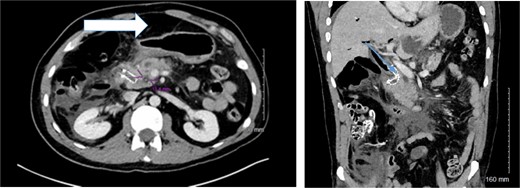

A 37-year-old male with a history of recurrent pyloric stenosis and choledocholithiasis, previously treated with laparoscopic Heineke-Mikulicz pyloroplasty, cholecystectomy, multiple pyloric dilations, and ERCP, presented with recurrent gastric outlet obstruction and bile duct obstruction. He underwent a complex ERCP procedure to extract a common bile duct stone and place a biliary stent. However, due to a deformed duodenum and complex biliary anatomy, the procedure was complicated by a large combined duodenal and bile duct perforation confirmed on CT-scan imaging (Fig. 1) 4 days later and necessitated urgent surgical intervention.

Preoperative and intraoperative findings of duodenal perforation and reconstruction. Preoperative CT- scan of the abdomen delineating the amount of free intra-peritoneal air (arrow) and the location of the biliary metallic stent (arrow).